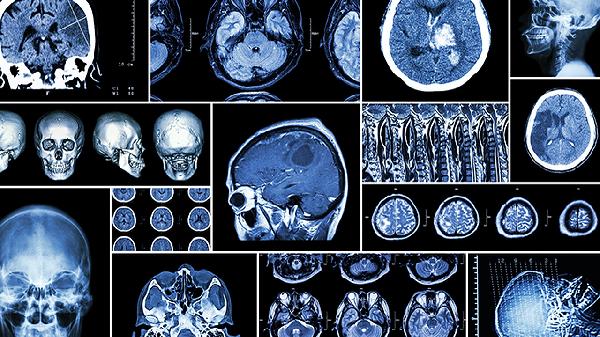

大脑迟钝注意力不集中可通过调整作息、认知训练、饮食优化、情绪管理和适度运动等方法改善。长期注意力障碍可能与神经功能失调或心理压力有关,建议结合专业评估制定个性化方案。